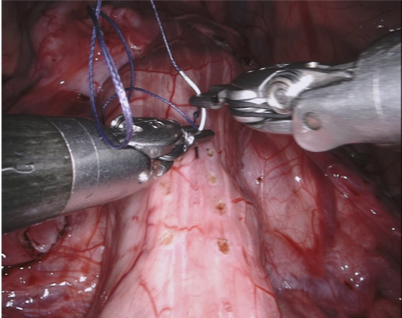

Our challenge was made up of 3 sub-problems. The first was binary instrument segmentation, where each frame was separated into da Vinci Xi instruments and a background class, which contained an ultrasound probe, surgical clips and porcine tissues. The second task was instrument part segmentation, where we scored the participants on whether they could correctly segment each articulating part of the instrument (see Fig. 3). Our final task was to segment and classify the instruments (see Fig. 4).

Our dataset was made up of 10 sequences of abdominal porcine procedures recorded using da Vinci Xi systems. From each procedure we selected active sequences where significant instrument motion and visibility was observed and sampled 300 frames at a rate of 1 Hz. In cases where instrument motion ceased for several frames we manually removed these frames and extended the sequence so that exactly 300 frames remained. We provided left and right eye images from the stereo camera on the Xi system and also provided camera calibration information in case participants wished to use stereo reconstruction as a feature.

We provided the first 225 frames of 8 sequences as training data and kept the last 75 frames of those 8 sequences as test data. 2 of the full 300 frame sequences were kept as test sequences. Test labels were kept hidden from the participants. Our datasets contain 7 different robotic surgical instruments. The Large Needle Driver, Prograsp Forceps, Monopolar Curved Scissors, Cadiere Forceps, Bipolar Forceps, Vessel Sealer and additionally a drop-in ultrasound probe, which is typically held in the jaws of the Prograsp Forceps instrument. Samples from the training datasets are depicted in Fig. 2 and examples of the different instrument types are shown in Figure 3 and 4.

In Fig. 10 we show qualitative results of randomly chosen frames from each dataset. In the top row, we show frame 278 from dataset 1, which contained 2 Prograsp Forceps instruments and a drop in ultrasound probe. The 3 selected frames were from methods that all averaged over 0.8 mean IoU yet showed considerable difference in their ability to differentiate the US probe. There was also visibly different performance across the methods in dataset 7, which contained a Vessel Sealer and complex lighting.